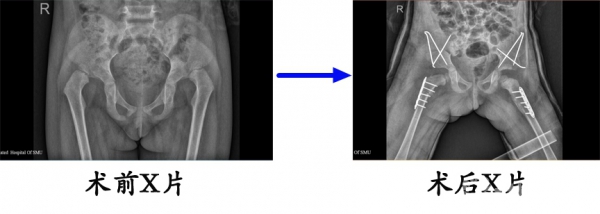

1.改良salter截骨

刘某某,双侧发育性髋关节发育不良,在我院行改良salter截骨后,复位良好。